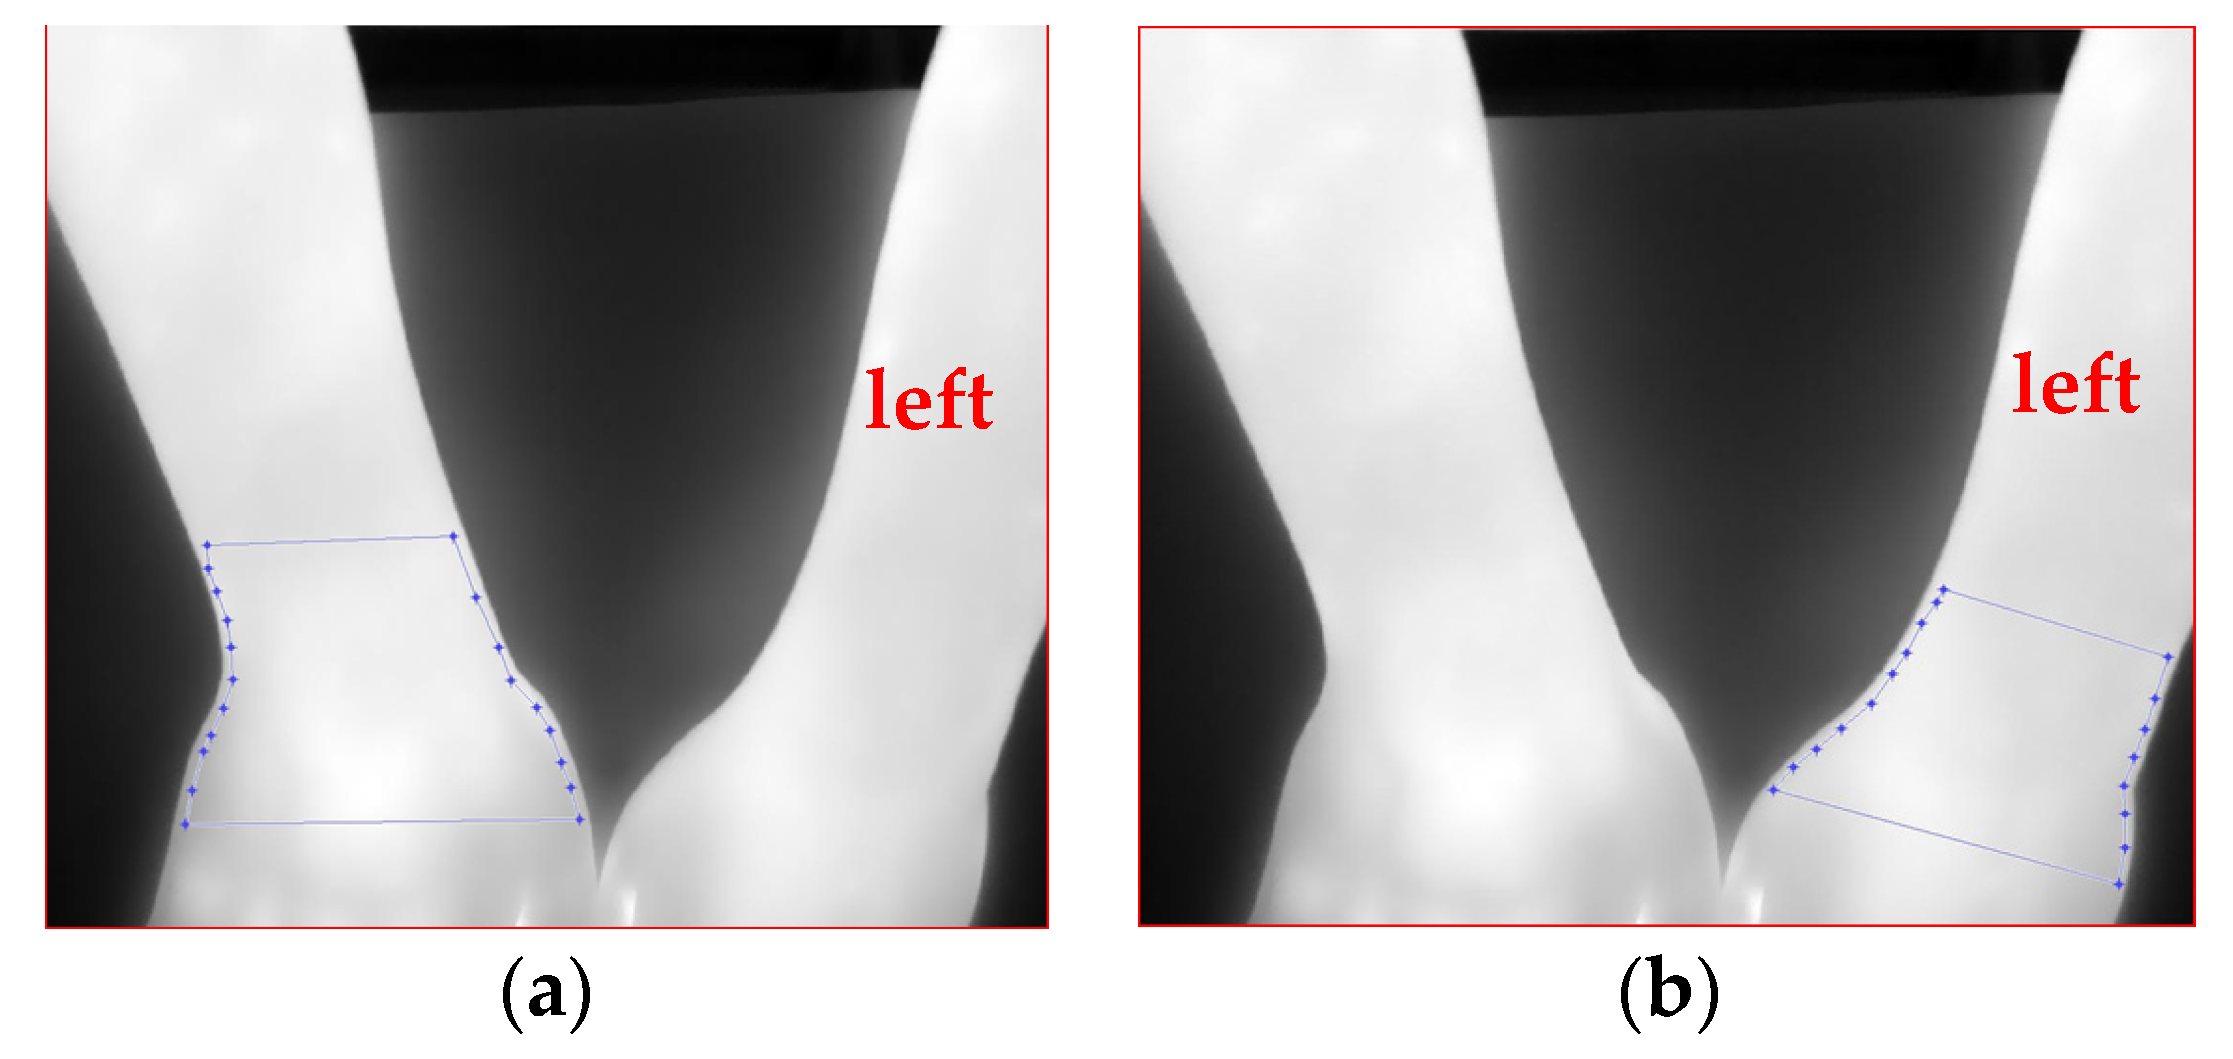

3.4.1. Selection of Region of Interest and Tracking

3.4.2. ROI Feature Extraction